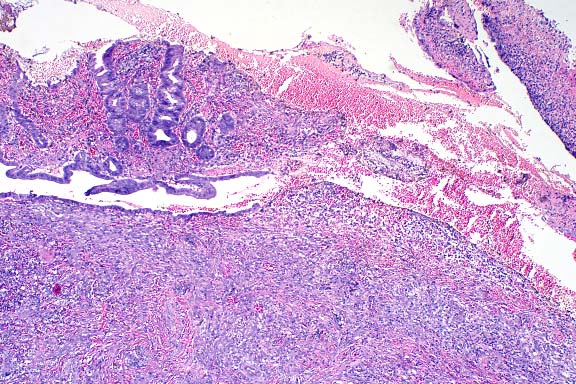

Because of the extensive destruction of the renal parenchyma in the Holsteiner horse, the kidney from the miniature horse was substituted for Wednesday Slide Conference. In addition to the renal and optic nerve lesions, both horses also had significant retinitis and encephalitis associated with the presence of the parasites. The enlarged testicle from the miniature horse also had a severe, diffuse, granulomatous orchitis associated with the parasite.

Identification of the parasite within tissues is based on the following criteria: a smooth, thin cuticle; platymyarian-meromyarian musculature; a pseudocoelom; a rhabditiform esophagus composed of a corpus, isthmus, and bulb; an intestinal tract composed of single nucleated, low cuboidal cells; flexed ovary and uterus; and a tapered tail. The flexed ovary and pointed tail differentiate this organism from other rhabditiforms.

Case 1-1. Kidney. Note tubular ectasia and proteinaceous debris, interstitial lymphoplasmacytic infiltrate, profiles of rhabditiform nematodes, and multinucleate giant cell. 10x obj.

1. Kidney: Nephritis, granulomatous, multifocal and coalescing, moderate to severe, with interstitial fibrosis, tubular ectasia, and many larval and adult rhabditid nematodes, Miniature horse, equine, etiology consistent with Halicephalobus sp.

2. Optic nerve (per contributor): Neuritis, necrotizing, granulomatous, diffuse, severe, with epineurial and perineurial fibrosis, and many larval and adult rhabditid nematodes, Holsteiner, equine, etiology consistent with Halicephalobus sp.